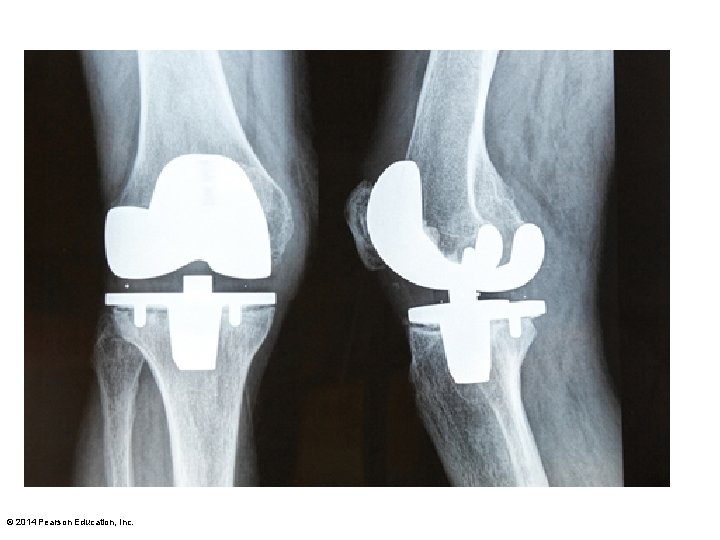

© 2014 Pearson Education, Inc.